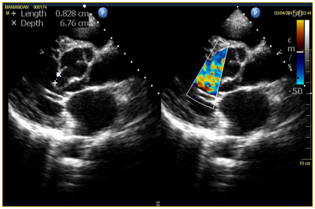

Sinus of Valsalva aneurysm is a rare congenital anomaly presents approximately in 0.09 % of population which occurs due to separation between the aortic media and the annulus1. It can be a silent asymptomatic aneurysm and detected incidentally or present as a catastrophic rupture in heart failure. The right sinus of Valsalva is most commonly involved (76.8%), followed by the non-coronary sinus, and, least commonly, the left coronary sinus (3%)2. Simultaneous involvement of right sinus and left sinus with rupture in to the left ventricle has not been reported in literature as far as our knowledge goes. Ruptured sinus of Valsalva aneurysm is rare but is usually diagnosed on echocardiography. Sinus of Valsalva has a higher male preponderance (4:1) and the incidence is higher in Asian populations2.The etiologycan be either congenital or acquired. Acquired conditions occurs less frequently and is usually caused by diseases affecting the aortic wall, such as infection (syphilis, bacterial or fungal endocarditis, and tuberculosis), degenerative disease (atherosclerosis, connective tissue disorders, and cystic medial necrosis), or thoracic trauma3,4. Un-ruptured conditions usually remain asymptomatic (Figure 2).

Figure 2 2A: Peroperative Probe demonstrating rupture of left sinus of valsalva in to the left ventricle.

2B: Peroperative probe demonstrating rupture of right sinus of valsalva in to the left ventricle.

In 1962, Sakakibara and Konno5 proposed the first formal classification system for sinus of Valsalva aneurysms, according to their site of origin and rupture. This anatomic classification system described only 4 types of aneurysms, arising from either the right coronary sinus or the non-coronary sinus, and did not include left sinus nor account for all possible chambers of penetration. The modified Sakakibara classification proposed by Xin-jin5 included Type 5 group which included other rare conditions (e.g., rupture into left atrium, pulmonary artery, left ventricle, or other structures). In the present case we found an additional sinus of Valsalva from right coronary sinus opening into left ventricle. We could not find any literature mentioning this condition to fit into any of the types even in the modified Sakakibara and Konno classification (Figure 3).

Figure 3 Postoperative Echo demonstrating no residual Rupture of sinus of valslava with well functioning mechanical valve in the aortic position.